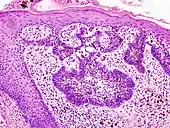

Basal cell carcinoma of the skin, cell nuclei (blue-purple), extracellular material (pink).